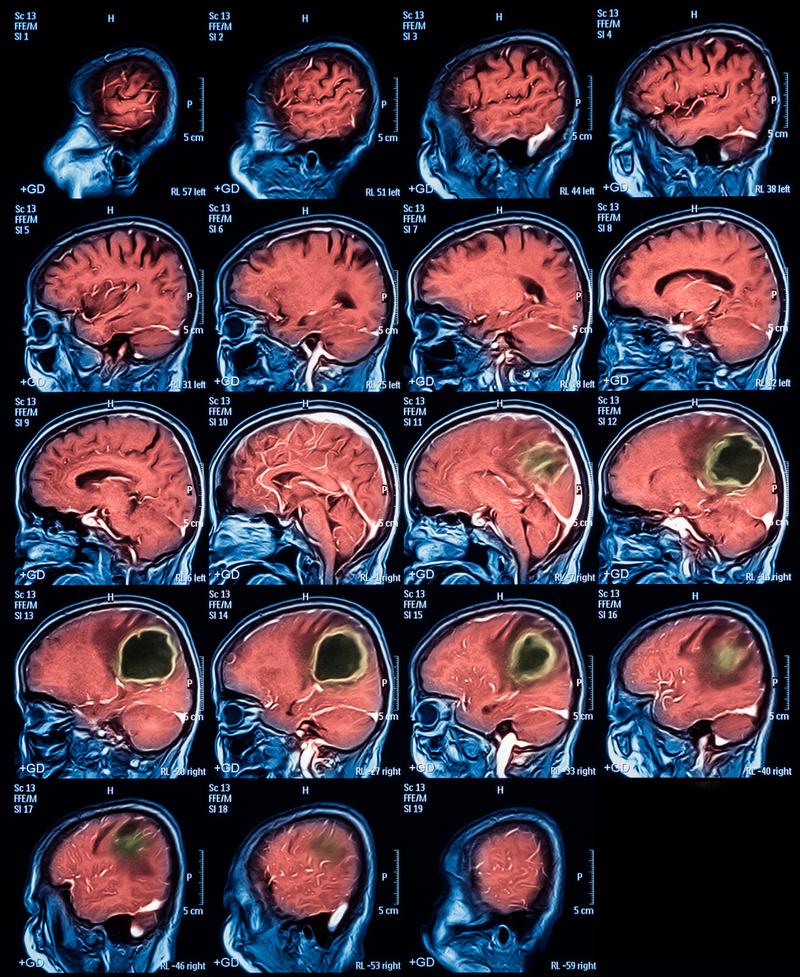

- 头颅MRI(磁共振成像): 这是诊断脑梗死最敏感、最准确的检查,尤其是在早期,MRI能比CT更早地发现缺血病灶,甚至可以在发病后几十分钟内就显示出异常,如果怀疑是脑梗,MRI是首选的后续检查。